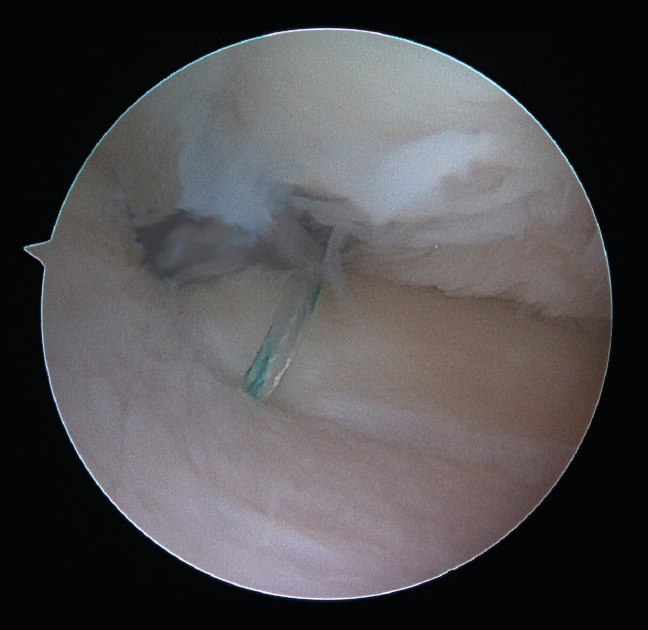

One of the patients in the standard guide group required modification of the perforation secondary to intraarticular exit of the Kirschner wire in a position different from that planned, due to positioning difficulties caused by the existence of a narrow intercondylar groove and prominent spines. The 3D printed guides adapted on both supports to the bone surface of the tibia and were precise in conducting the guide needles towards the planned position (Figures 6 and 7). There were no problems derived from friction between the metal of the needles and the bore of the customized guide, and handling was ergonomically satisfactory for the surgeon.

Figure 7. Final repair (right knee).